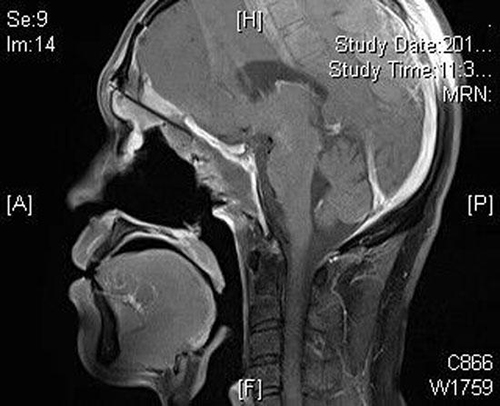

据山东省立医院耳鼻喉科时光刚主任介绍,患者30岁,男性,因头疼、左眼视力下降、仅存在光感,来院就诊。经影像学检查,确诊为巨大鼻颅底肿瘤,且已经向上侵犯前颅底,如不及时切除,将会侵犯大脑、颈内动脉、颅神经,最终会危及患者生命。

在由耳鼻喉科时光刚主任率领的鼻颅底外科团队,及神经外科许尚臣主任医师,麻醉科王公明主任医师和护理人员胡姗姗等多学科团队的共同努力下,为患者成功实施手术,术后外科ICU进行了协助管理。目前,经过术后2月余的随访观察,复查颅脑MRI提示肿瘤彻底切除,内镜检查提示鼻颅底缺损愈合好,实现临床治愈。